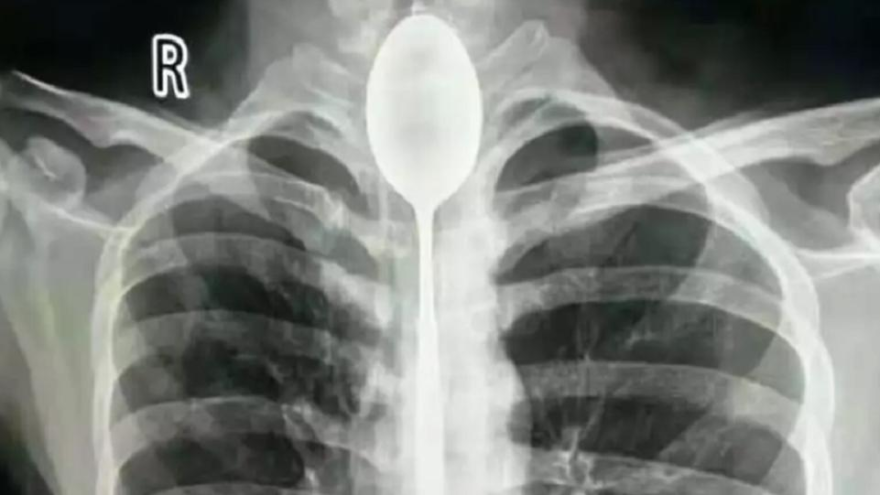

Abone OlÇin'de nefes almakta zorluk yaşayan bir kişinin boğazında 20 santimlik kaşık çıkarıldı.

Çin'in Sincan Uygur Özerk Bölgesi'nde nefes almakta zorluk yaşayan bir kişinin boğazından 20 santimlik bir kaşık çıkarıldı. Kaşığı yutan kişi, bunu bir yıl önce arkadaşlarıyla girdiği iddia sonucunda yaptığını açıkladı.

İsminin Zhang olduğu öğrenilen şahıs, ‘yapabildiğini göstermek için’ 20 santimlik bir kaşığı yuttu ve uzun süre bu şekilde yaşadı. 20’li yaşlarında olan Zhang, göğsünden yumruk yiyene kadar boğazındaki kaşıkla ilgili herhangi bir problem yaşamadığını belirtti.

Çin’in ünlü sosyal medya platformlarından weixin’de yer alan açıklamada, nefes almakta güçlük çektiğini belirterek hastaneye giden Zhang’la ilgili yapılan incelemeler sonucunda, şahsın boğazındaki kaşık tespit edildi ve acilen ameliyata alındı.

İki saatten fazla süren operasyonun ardından Zhang’ın boğazındaki kaşık çıkarıldı.

Zhang’ın ameliyatını gerçekleştiren doktorlardan Yu Xiwu, yaptığı açıklamada, “Çok şaşırdım, daha önce böyle bir olayla karşılaşmamıştım” ifadelerini kullandı. Hastane tarafından yapılan açıklamada, Zhang ‘şanslı’ olarak nitelendirildi ve metal objeleri yutmanın hayati risk taşıyabileceği vurgulandı.

Doktorlar ayrıca kaşığın ciddi bir enfeksiyona neden olabileceğini söyledi.